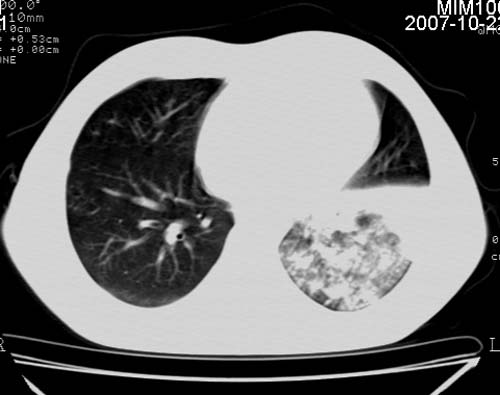

男,21岁,咳嗽、胸闷、乏力伴多汗二十余日、无明显发烧。患者一般情况好,为初三学生。

右肺上叶前段及左肺下叶多形性病变伴厚壁空洞,周边示树芽征.左肺下叶不张改变.

考虑;肺结核,不除外左肺下叶支气管内膜结核.

双肺继发性肺结核伴左侧空洞形成!不除外合并霉菌感染!(双肺多发病灶,左侧病灶形成空洞,并空洞内见壁结节。建议改变体位,观察空洞内结节情况,以便排除霉菌感染!)